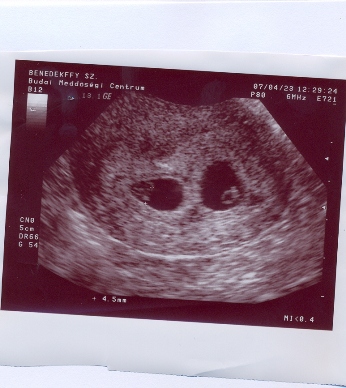

Gratula az ikrekhez és természetesen üdv nálunk